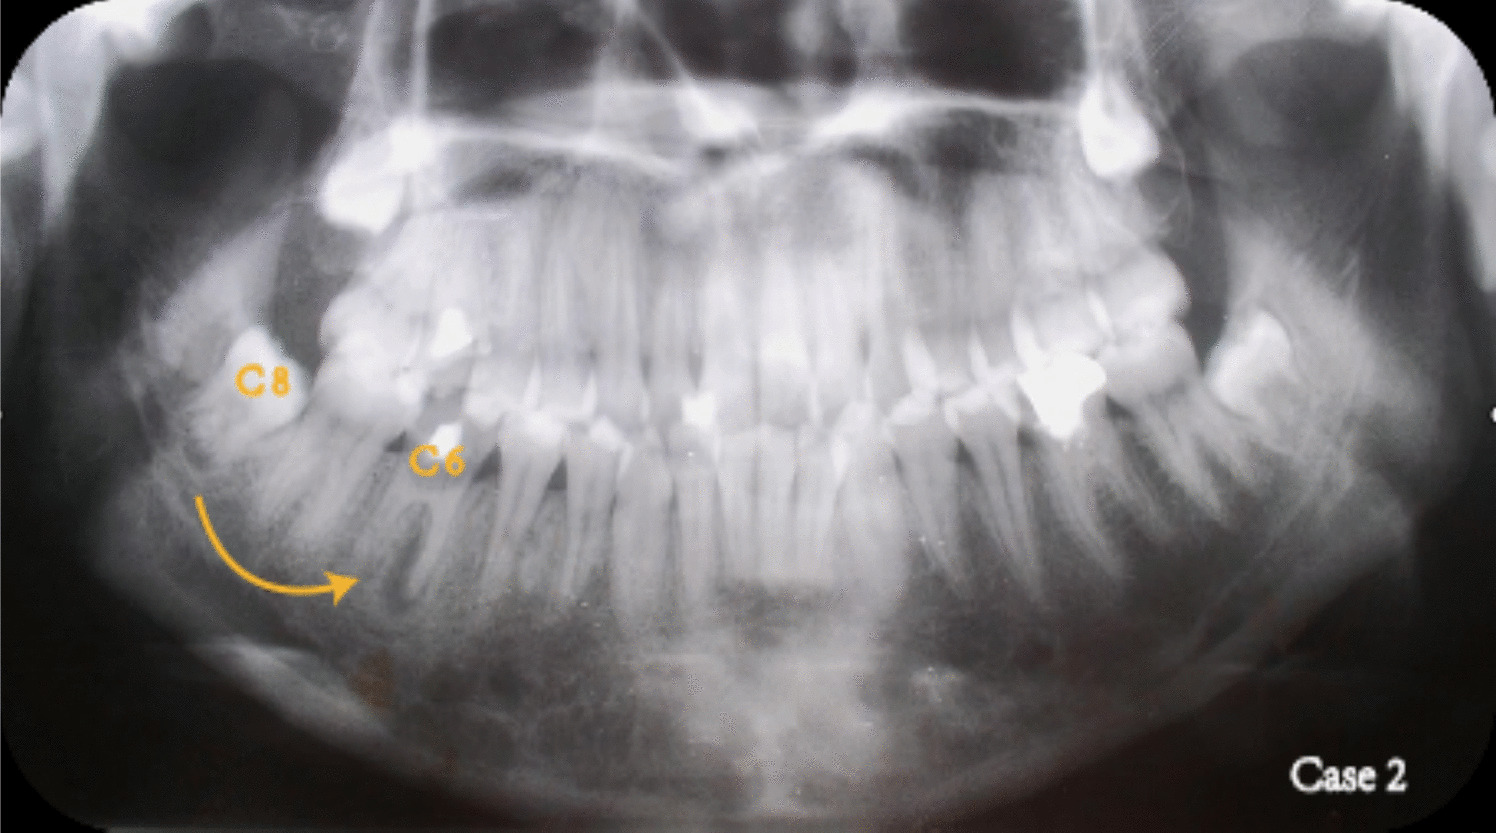

Case 2

A 39-year-old female patient was evaluated in September 1992 at the Oral-Dental Surgery Department of Peking Union Medical College Hospital. The tooth 46 exhibited extensive decay extending to the subgingival with periapical periodontitis. The tooth was deemed non-restorable and recommended for extraction and subsequent restoration. Imaging studies revealed that the lower right third molar possessed favorable morphology and structure (Fig. 14), being in an early stage of development, which would facilitate initial stability and reconstruction of the pulp after transplantation. Consequently, a treatment plan was devised whereby tooth 48 was transplanted into the position of the missing tooth following the extraction of tooth 46.

Fig. 14

Preoperative panoramic radiograph and the treatment planning